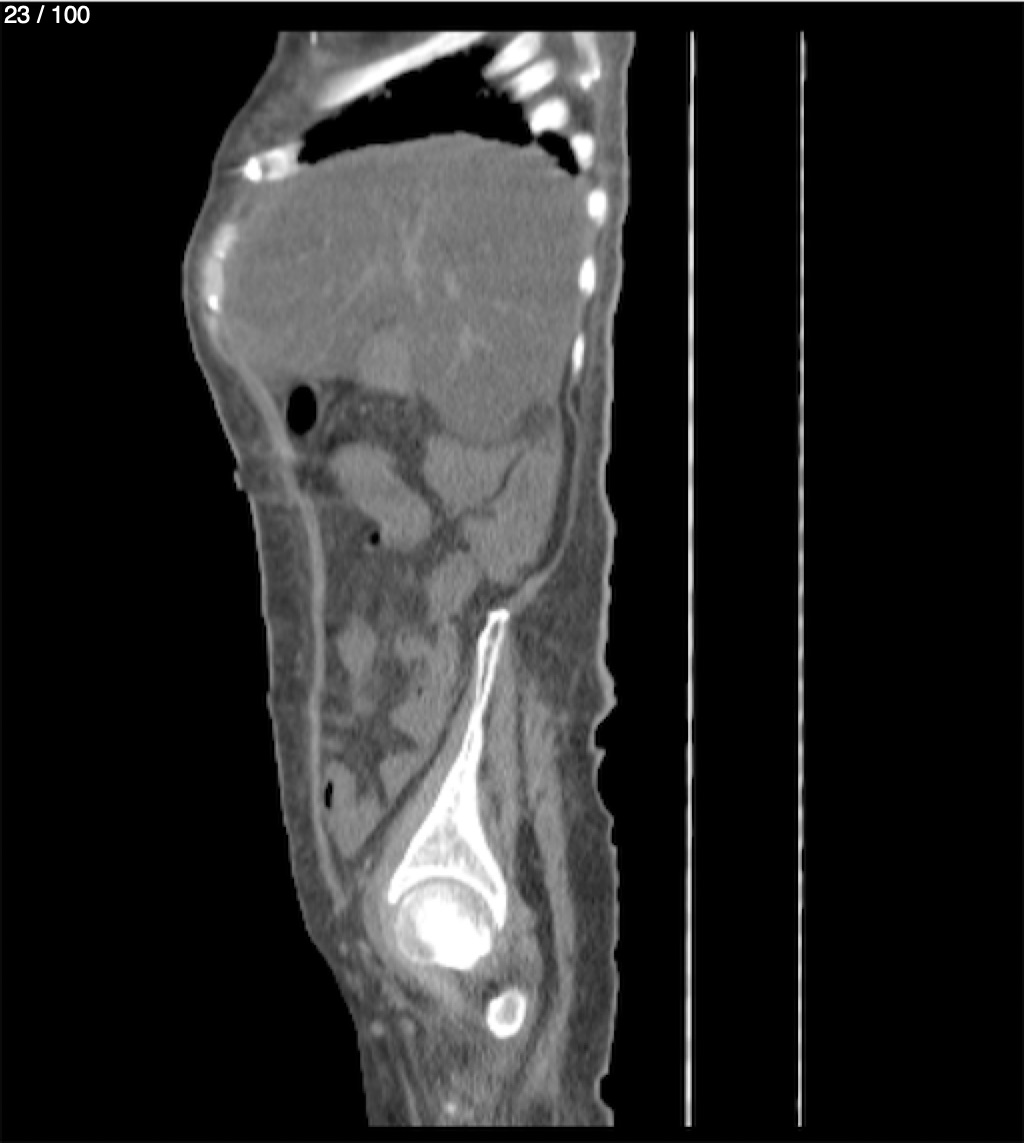

Hilda Geronimo Mendez 60A - T.C Abdomen Simple